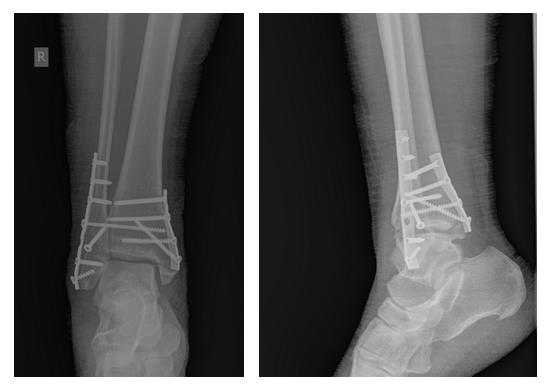

В день обращения пациентка послоностью обследована, проведено оперативное лечение, открытая репозиция, остеосинтез перелома нижней трети малоберцовой кости пластиной, внутренней лодыжки винтом, внутренняя лодыжка дополнительно фиксирована анкерным фиксатором.

На контрольных рентгенограммах после операции положение отломков, металлофиксаторов правильное, подвывих таранной кости устранён.

В связи с выраженным отёком мягких тканей, высоким риском некроза краёв ран и инфекционных осложнений пациентке с целью предоперационной подготовки выполнялись скелетное вытяжение, сосудистая и метаболическая терапия, лимфодренаж, физиотерапия. После спадения отёка, на 3 день после поступления выполнено оперативное вмешательство: открытая репозиция, остеосинтез переломов наружной и внутренней лодыжек пластинами и винтами.